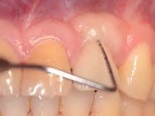

Fig 14. At 3 months after laser treatment, there was absence of bleeding on probing, and shallow probing depths of only 3 mm compared to pre-treatment.

Figure 14